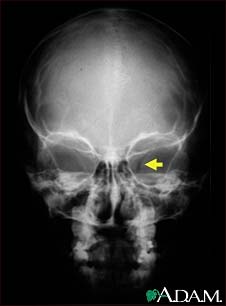

Neurofibromatosis I, enlarged optic foramen

This X-ray shows the skull of a child with neurofibromatosis (NF-1). This child developed visual difficulties and was discovered to have a glioma (nerve tumor) in the optic nerve. The tumor has enlarged the bony opening (optic foramen), through which the optic nerve passes. This can be seen on the right side of picture.